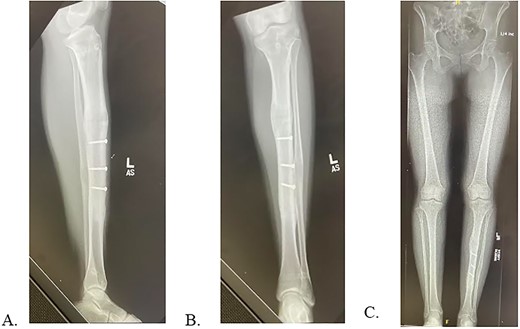

Final radiographs showed adequate alignment, internal fixation of the tibial osteotomy, and complete hardware removal aside from the three new fixation screws (Fig. 4A). The incisions were closed, dressed and the leg was immobilized in a Controlled Ankle Motion (CAM) boot. The patient spent six weeks non-weight bearing but was able to return to work without any pain or limping at three months post implant removal (Fig. 4B). Final 12-months follow-up demonstrated radiographically healed osteotomy site and maintained equal limb lengths and alignment (Fig. 5A-C).

A: Intraoperative radiograph demonstrating complete implant removal with x3 fixation screws. B: 6 weeks postoperative radiographs demonstrating maintained alignment at osteotomy site.